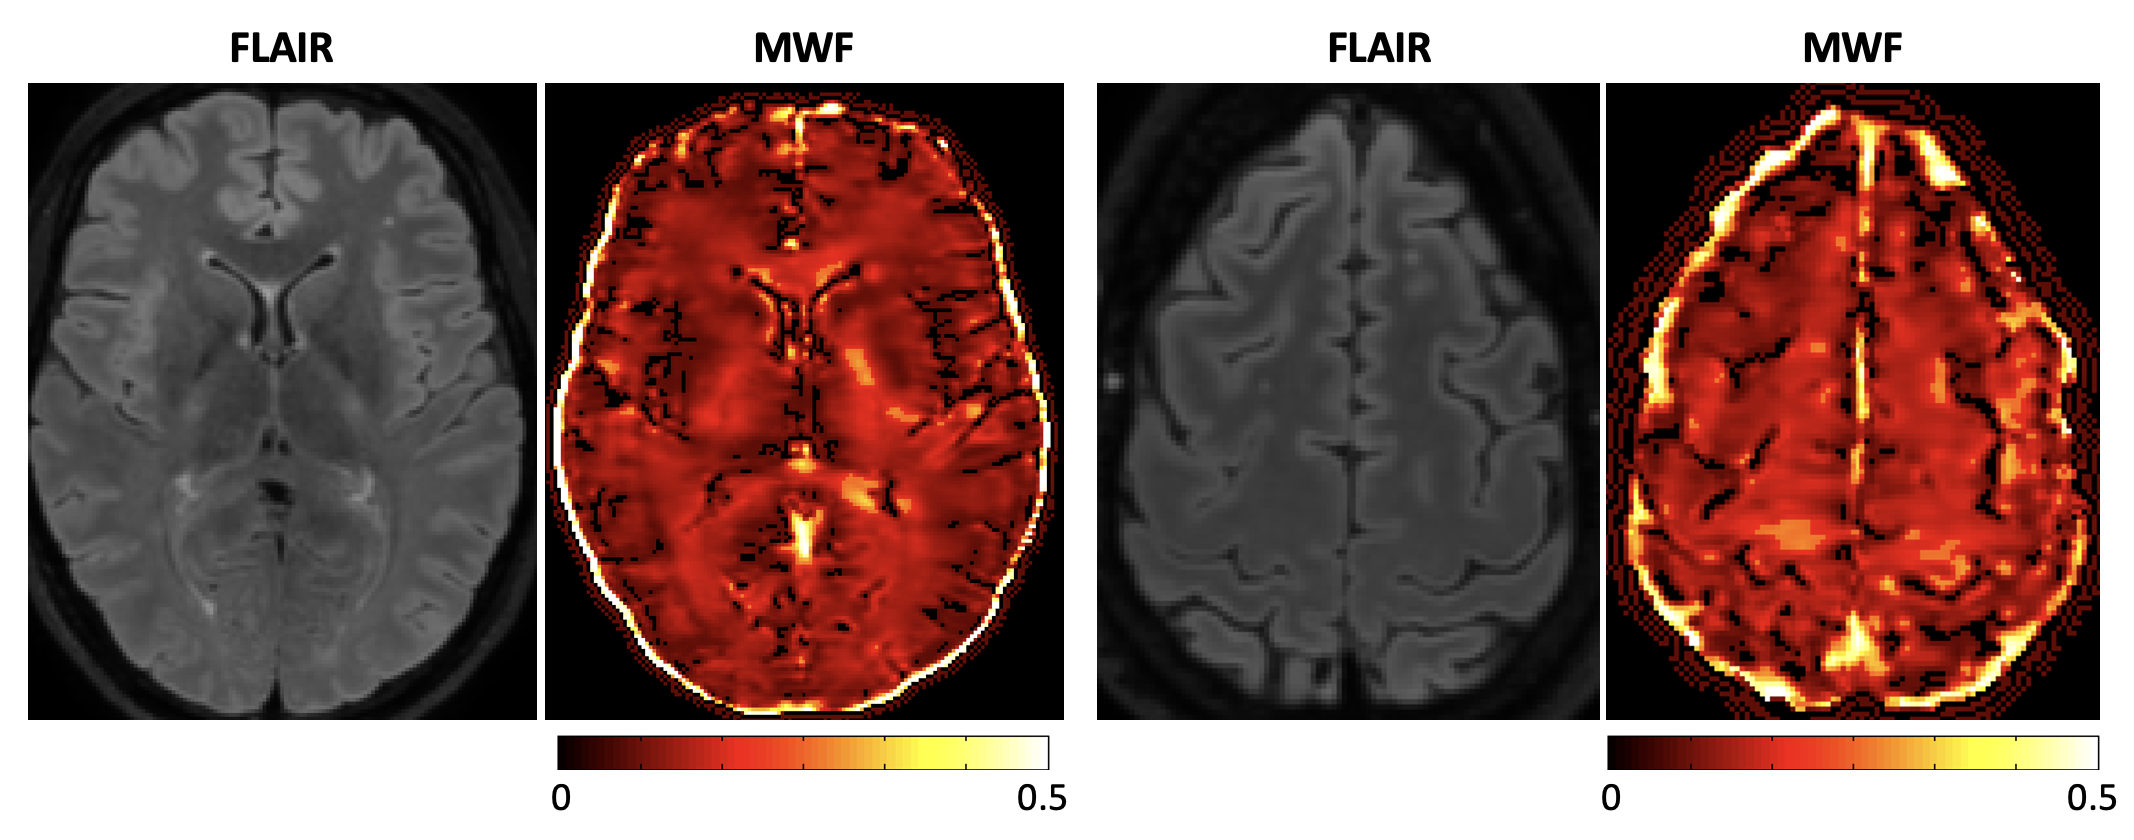

Background

This study explored whether Myelin Water Imaging could detect myelin injury in Anti-NMDA receptor autoimmune encephalitis (NMDAr-AIE), where traditional neuroimaging is often normal. Myelin Water Fraction (MWF) quantifies myelin content by distinguishing myelin sheath water from other brain water compartments.

Methods

Adult participants with confirmed NMDAr-AIE diagnoses and healthy controls (HC) underwent 3T brain MRI (Magnetic Resonance Imaging) including MWF mapping. Participants were recruited after discharge from the hospital. Mean MWF was calculated for 4 white matter regions of interest (ROI). MHI (Myelin heterogeneity Index) was calculated by dividing the MWF standard deviation by the mean MWF. Patient demographics, clinical assessments, treatment, and outcomes were collected.

Results

Fig. 1 Myelin Water Imaging of two selected patients

Screenshot 2025 06 01 at 12.05.23 pm

Myelin Water Imaging showed no myelin pathology in five NMDAr-AIE patients, with MWF and MHI values comparable to HC, suggesting that myelin pathways are relatively preserved post-recovery from AIE. Moving forward, we aim to continue recruiting healthy controls, patients post-recovery and those experiencing active disease to determine if there are any MWF abnormalities throughout the disease course. Future studies are needed to assess MWF changes in other antibody-mediated encephalitides.